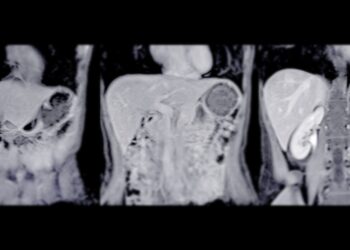

Osteoartritas – tai dažniausiai pasitaikantis sąnarių sutrikimas, kurį nulemia laipsniškas sąnarių kremzlės nusidėvėjimas. Šios ligos metu kremzlė, paprastai apsauganti sąnarinius...